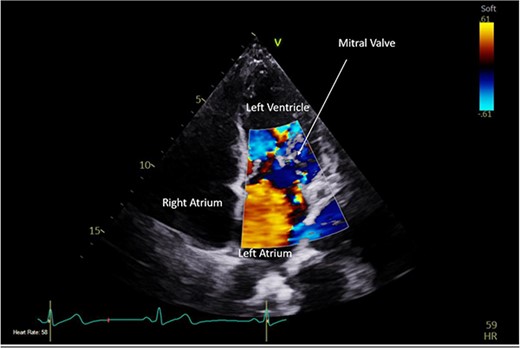

A CTPA was undertaken on Day 2, which excluded pulmonary embolism but confirmed bilateral peri-hilar consolidation and pleural effusions consistent with pneumonia. However, her pulmonary artery was dilated at 32 mm indicative of potential heart failure. On Day 5 of her ICU stay, a transthoracic echocardiogram was undertaken that revealed there to be severe mitral regurgitation including a mobile echogenic mass attached to the underside of the anterior mitral valve leaflet consistent with a vegetation (Figs 1 and 2).

Pre-operative TTE depicting mitral valve with vegetation (labelled).